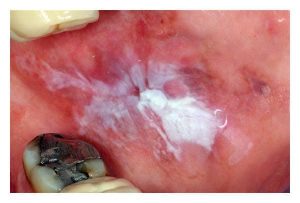

Amalgam Ve Kandidiyazis Candida

Fotoğrafların ortak yönü : amalgam-kandidiyazis

Kandidiyaz, genellikle toksik yükleri yüksek olanlar ( (metal maruziyetleri, özellikle test sonucunda cıva veya diğer toksik metallere karşı immün reaktif olduğu tespit edilenler ) gibi immün sistemi baskılanmış kişilerde görülür.

Güvenlik önlemli amalgam replasmanı ve cıva detoksu, Candida’yı iyileştirir veya önemli ölçüde hafifletir.